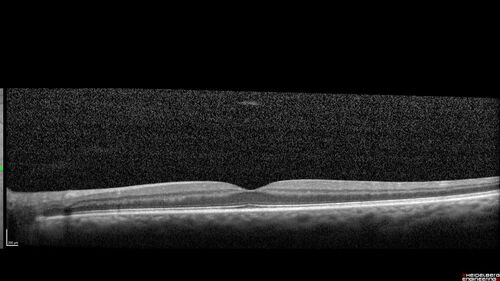

Acute retinal necrosis

67 year old female Hazy vision in the right eye for 5 days.

Medical Hx: TYPE 2 DIAB.. Hypercholesterolemia.

Systemic Meds: CRESTOR 10 MG QD. METFORMIN 500 MG QD. PROLIA Q 6 MOS. SULFA 800 MG/ TRIMETHOPRIM 160 MG TID. VALCYCLOVIR 1 GM TID. PROBIOTIC QD. CENTRUM 50+ QD. ALLERGY MED QD

VA 20/40, 20/20

IOP 19, 12

SLE: Trace AC cell OD and moderate vitreous cell OD